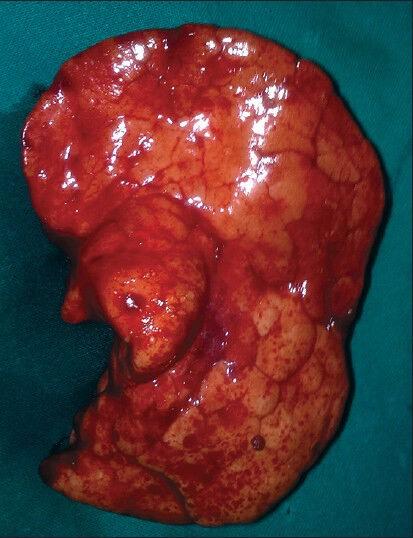

Congenital lobar emphysema (CLE) is a rare congenital anomaly of lung causing over aeration of one or more lobes of a histologically normal lung. It presents in infancy with respiratory distress due to compression atelectasis and often associated with mediastinal shift and hypotension. CLE poses a challenge in diagnosis and positive pressure ventilation due to air trapping. We report a case of 8-week-old infant with CLE posted for right lobectomy. Strategies to prevent misdiagnosis, over aeration and use of IPPV have been reviewed.

先天性肺叶气肿(CLE)是一种罕见的先天性肺部异常,可导致组织学正常的一个或多个肺叶过度充气。它在婴儿期因压迫性肺不张而出现呼吸窘迫,常伴有纵隔移位和低血压。由于气体潴留,CLE在诊断和正压通气方面构成挑战。我们报告一例8周大患有CLE的婴儿拟行右肺叶切除术。已对预防误诊、过度充气和使用间歇正压通气的策略进行了综述。